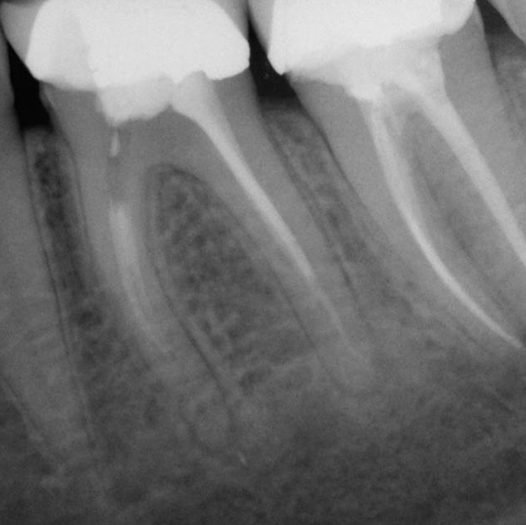

Before

Before Root Canal treatment